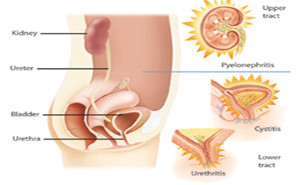

Asymptomatic bacteriuria (ASB) is

seen in some healthy female populations and many women or men

with genitourinary tract abnormalities.

Although in many clinical

situations ASB is harmless, many patients with ASB are treated unnecessary.

Especially, long-term antimicrobial therapy of ASB may select for superinfection

with more antimicr...